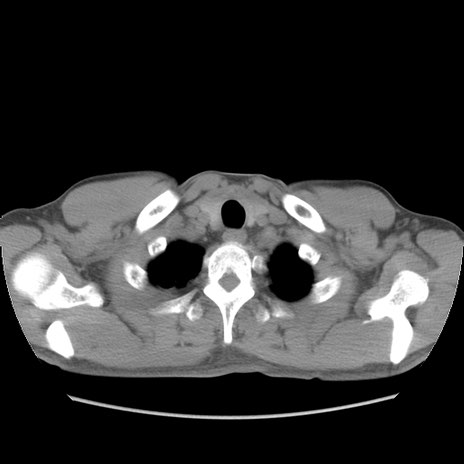

症例56 CT(横断像)

脂肪ウインドウ